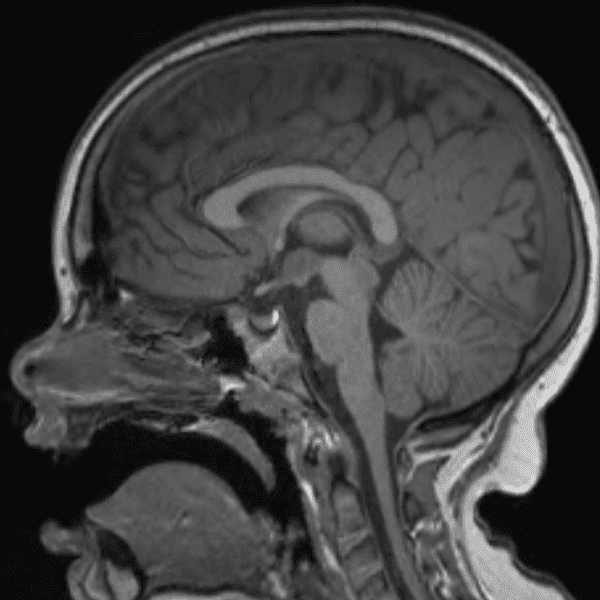

Classic Cases